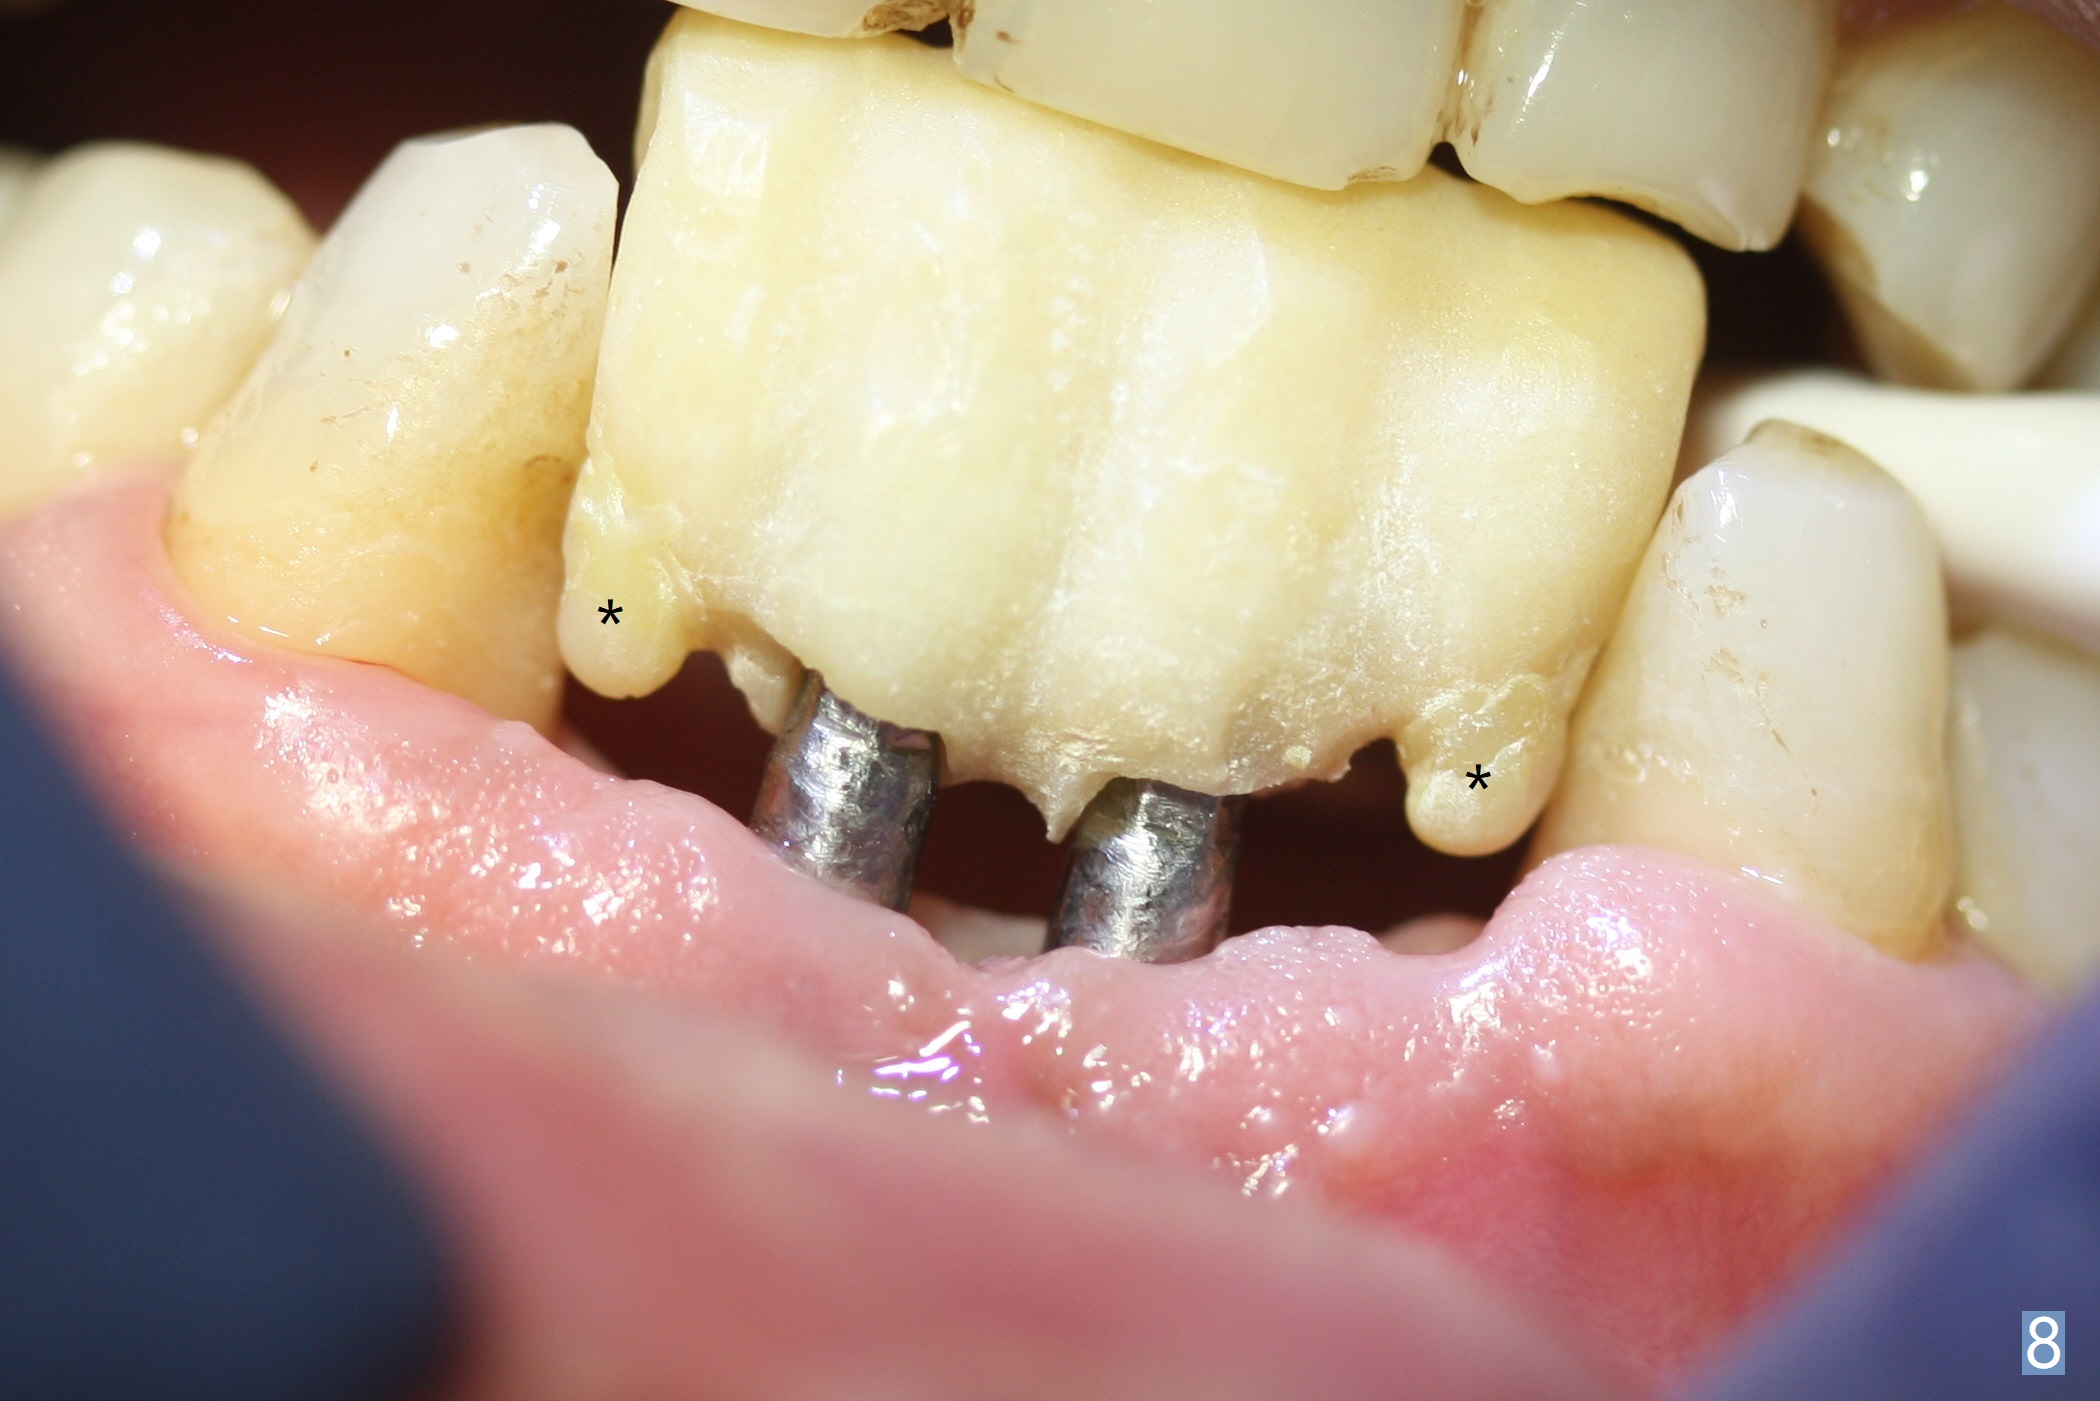

When the patient (smoker) returns for treatment, the apical abscess associated with #25 and 26 reduces with oral Amoxicillin. He agrees with 4 incisor extraction because of 2 apical fistulae (Fig.1 >). Osteotomy starts at the central incisor sockets due to mesial root exposure of the canines (Fig.2 arrowheads) and buccal alveolar bone fracture between #23 and 24 (Fig.7). Two of 3x14(4) mm 1-piece implants are placed with ~ 2 mm buccal gap (Fig.3). After Vanilla graft is placed in the bony defects (Fig.5 *) and Osteogen plug, sutures are placed (Fig.4). The implants are then placed deep to decrease thread exposure (Fig.6). Periodontal dressing is applied instead of provisional. Alveolar bone fracture between #23 and #24 accounts for why an implant is less suitably placed at #24 (Fig.7). Three months postop, composite is added to the pontic areas of the provisional (Fig.8 *). When the provisional is seated, the convex pontics press the used-to-be-flat gingiva (Fig.9 arrows). Thus the concave gingiva forms (Fig.10 *) with corresponding papillae (^). In fact the photos of Fig.8-10 is taken ~3 weeks later. Most of the grafted bone remains in place 3.5 months postop (Fig.11). A piece of floss with 2 knots in one end is placed between the middle units of the final bridge before cementation (Fig.12 (4 months 10 days postop)). In fact removal of residual cement is not so simple. It is tedious (Fig.13,14). An asymptomatic buccal fenetration with implant thread exposure is found 2 months post cementation and persists for another month in spite of advice to reduce smoking (1/2 ppd) and use of water pik (Fig.15). The area will be debrided, followed by bone graft and PRF in a month.